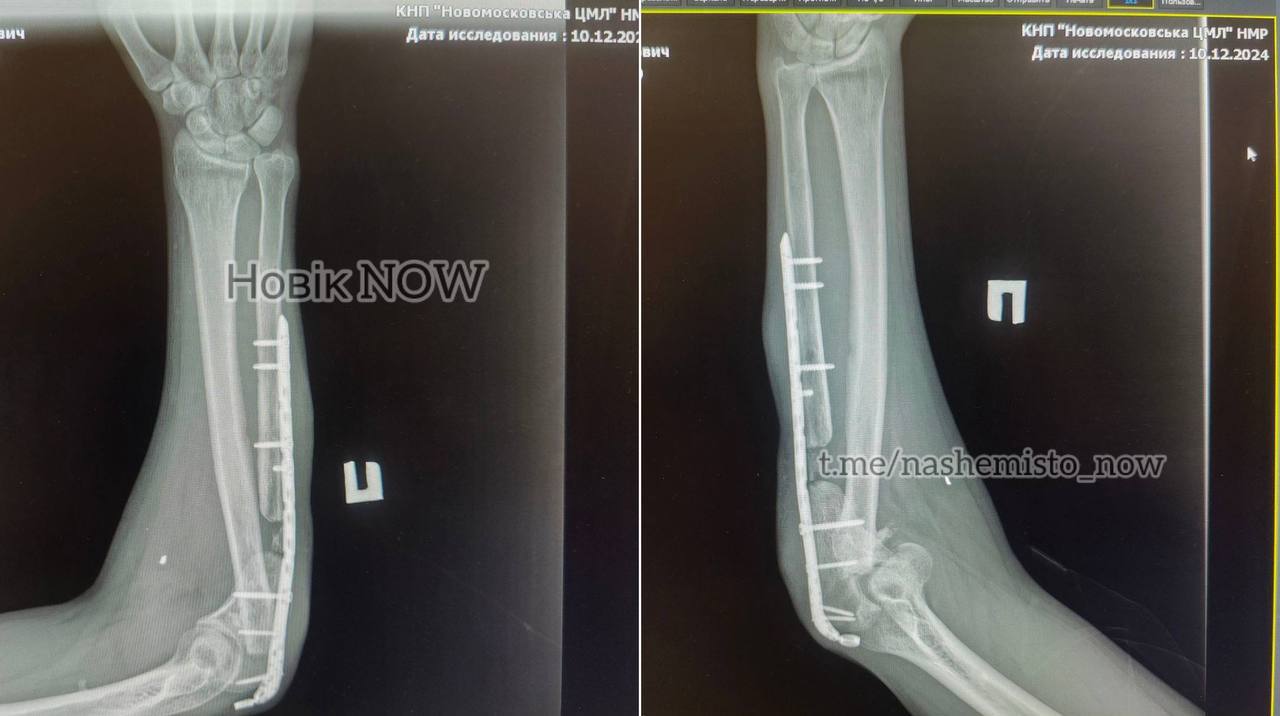

Пізніше у мережі опублікували фото, яке є доказом того, що у військового стоїть металева пластина в руці.

picture